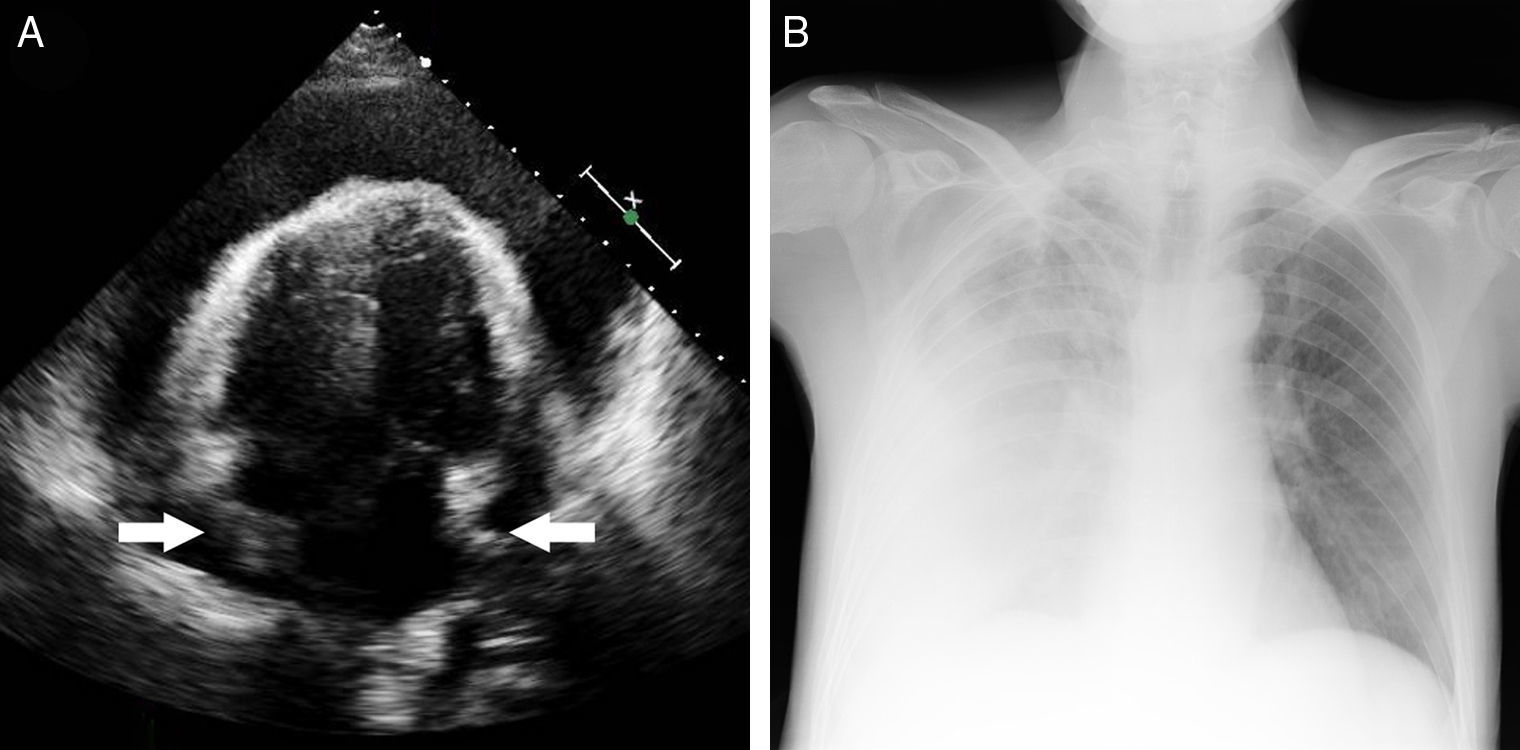

Recurrent Pericarditis as the Presenting Form of Adult Still's Disease

Pericardial Effusion A Novel Presentation of Aplastic Anemia Cureus Signs Of Haemodynamic Compromise What are the vital signs for hemodynamic monitoring? The patient’s vital signs should be measured and documented. Very fast or very slow pulse (fast can be either a reaction to or a cause of instability; Although clinical signs of hypoperfusion like altered mentation, oliguria and mottling of the skin; Common signs or symptoms of hemodynamics issues. Problems with your hemodynamics. Signs Of Haemodynamic Compromise.